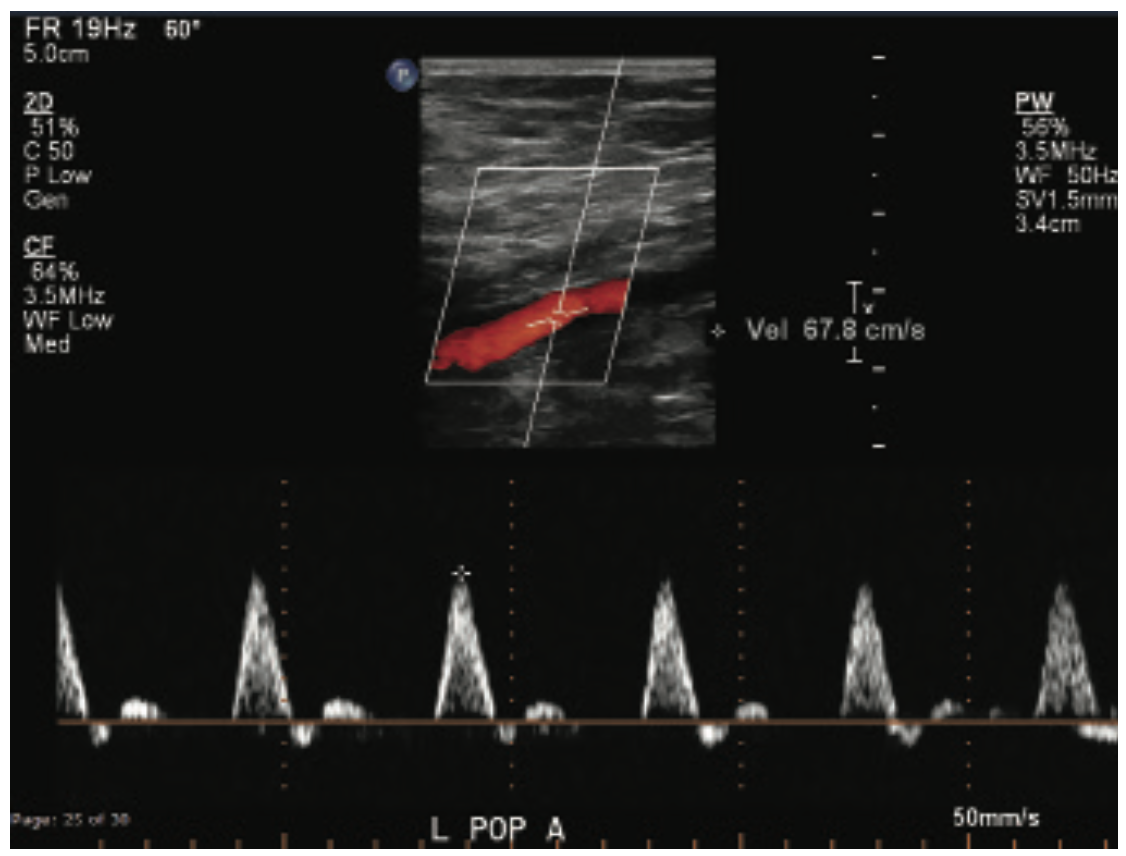

This is a 71-year-old male with a prior history of aortic valve replacement on coumadin, peripheral arterial disease, myocardial infarction, diabetes, and chronic kidney disease. He presented with a 3-month history of ischemic rest pain involving the left lower extremity, no wounds. He had previously undergone left superficial femoral artery (SFA) stenting for a chronic occlusion, but despite this, continued to have rest pain with peroneal-only runoff (Figures 1-4). He was brought in for left anterior tibial artery recanalization.

The patient qualified for the MicroMedical MicroStent trial, and both antegrade left lower extremity and retrograde dorsalis pedis access were obtained. The TASC II type D lesion of the anterior tibial artery origin was crossed with a V-18 wire (Boston Scientific), from below, and the wire was externalized via the antegrade sheath. Additionally, an .014-inch wire and balloon were placed into the tibioperoneal trunk and a 3 mm balloon was inflated across the origin of the anterior tibial artery. This “SOBE balloon protection technique” was used both to mark the origin of the anterior artery as well as serve as a buttress for placement of the stent (Figure 5). A 3 mm x 40 mm MicroStent was chosen and advanced through the 3 French (Fr) sheath from the dorsalis pedis access to the anterior tibial artery origin. The stent was placed across the lesion with precision to the origin. A 3 mm balloon was then inserted through the portal access and the stent was dilated to profile. Then the tibioperoneal trunk balloon was deflated and completion angiography was performed. Inline flow had now been created to the foot via the peroneal and anterior tibial arteries (Figure 6).

This patient had significant tibial disease involving the ostia of the vessels. He didn’t have wounds, but he did have rest pain. There are two reasons this patient was a good candidate for the MicroStent and the SOBE balloon protection technique: the tibioperoneal trunk was open so there was a way to cross the origin of the AT, and size-wise, it was a 3 mm vessel (and the bigger, the better, with the tibials). As Dr. Jihad Mustapha has reported, tibial sizing is important, whether confirmed angiographically or by intravascular ultrasound (IVUS). The anatomy was good; there was a short lesion at the anterior tibial origin and we were able to cross that area to put up the balloon in order to protect the origin. The stent had a perfect landing. In general, when I place tibial stents, it is nice to have a focal, shorter lesion, because patency tends to be better in that situation.